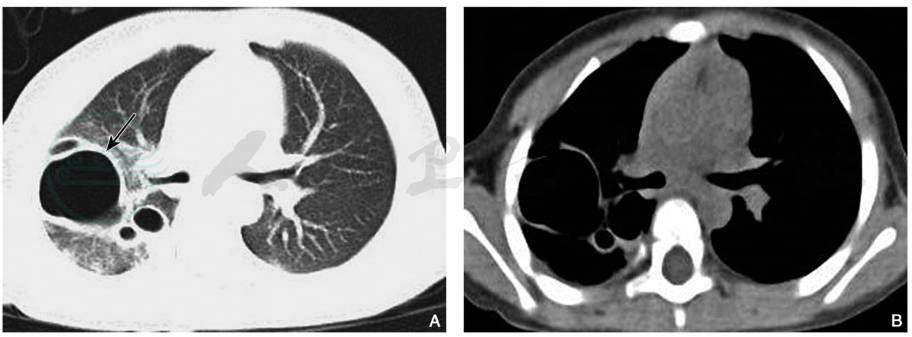

肺挫伤的主要CT表现为创伤应激引起肺间质和肺实质内的液体渗出,可分肺间质型和实变型。多在创伤后1~24小时出现局限性或弥漫性渗出肺泡性和间质肺水肿,以及大片血性渗出的肺实变影。早期CT表现为局部肺纹理增浓,云絮状及弥漫性磨玻璃状密度影,肺内或胸膜下区的无实性成分的或边界模糊的半透明磨玻璃状密度影为其特征性表现,其内尚可见血管和支气管影(图1)。病变可以是单侧、双侧受累,或出现多发性病灶。随局部肺组织内出血性渗出的增多,则可演变为有实性成分的磨玻璃密度影,表现为磨玻璃影内有斑片状影,或表现为大片密度增高实变影,内可见充气支气管影,或形成局部实变的肺血肿。本组实变病变主要分布于下肺基底部,并伴有不同程度的胸腔积液和肋骨骨折。

图1肺挫伤

女性,64岁,胸部CT轴位肺窗(A、B)显示两肺野内多发斑片状高密度影,边缘模糊,右侧胸膜局限性增厚

引自:中华影像医学·呼吸系统卷.第3版.ISBN:978-7-117-28903-0.主编: